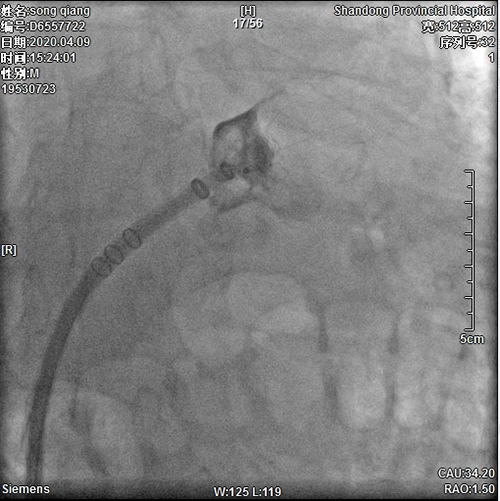

4月9日,伟德1949官方网站(山东省立医院)心内科主任医师朱贵月在介入诊疗科成功实施一例房颤左心耳封堵手术,其首创的RAO 35º+上腔静脉造影指引下房间隔穿刺术,经猪尾导管造影显示左心房从而直观的进行房间隔穿刺。这是一个业务创新。